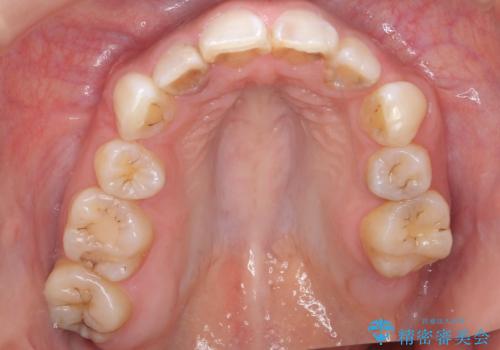

精査したところ、左上の奥歯の間(左上56間)にう蝕を認めました。

う蝕を丁寧に除去したのち、セラミックインレーによる修復を行いました。

セラミックインレーの審美的な仕上がりと自然な咬み心地にご満足頂けました。

「フロスを通したときの嫌な臭いもなくなった」と喜んで下さいました。

インレーの種類:セラミックインレー(e-max press)